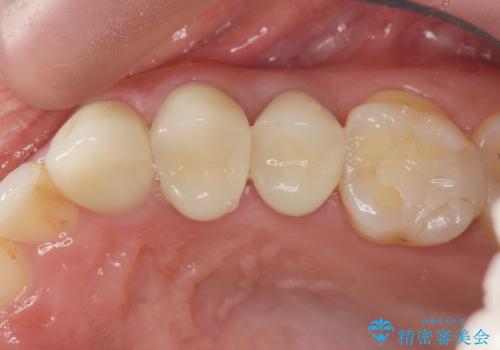

X線撮影を行い、隣接面に多発した虫歯と歯ぐきよりも深くなってしまった虫歯を小矯正をおこなったのちのセラミック治療で問題を解決します。

- 47.3万円(仮歯×3・ファイバーコア・ジルコニアクラウン×3・部分小矯正)費用は治療当時の料金となります

小矯正を行い深い虫歯を改善した後は、小手術を行うことで歯ぐき・周囲歯槽骨の状態を整えることでより安定した歯周環境を得ることができます。